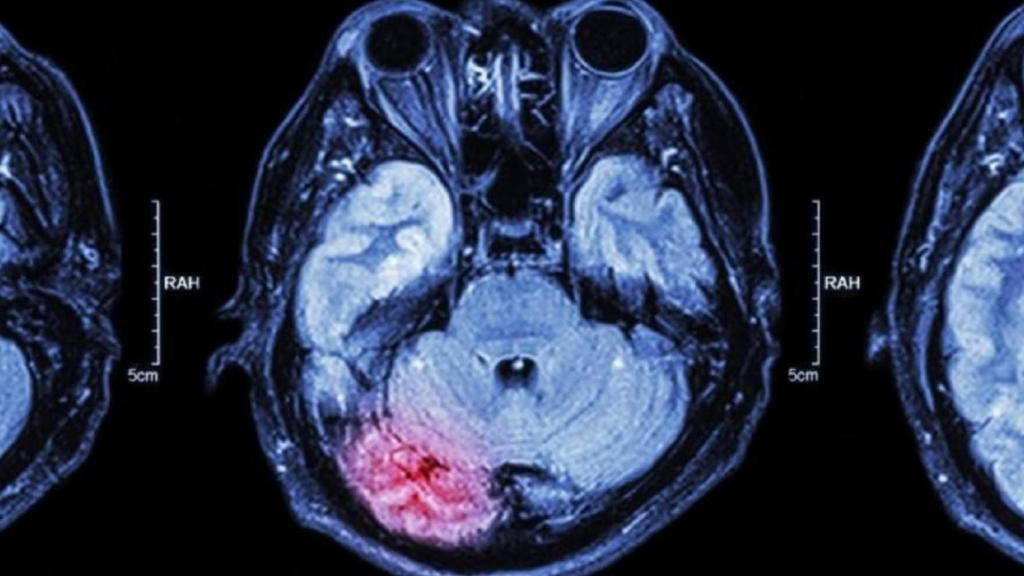

Un escáner cerebral.

Un escáner cerebral. iStock